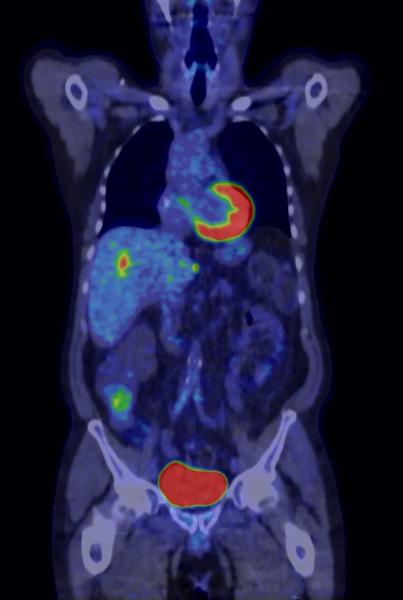

PET/CT helps bring personalized medicine within reach of practitioners. (Image courtesy of GE Healthcare)

Evolving these biomarkers into targets for molecular imaging is beginning to provide the means to verify disease processes early in their development. They are also showing promise as the means to monitor the impact of therapy, as well as the recurrence of these processes after therapy has initially succeeded.

Moreover, advances in molecular imaging scanners are providing the means to more precisely visualize and even quantify these processes. As research continues into the genes that may form the soft underbelly of human disease, new and more specific biomarkers will emerge. These will translate inevitably into more personalized healthcare with tailored solutions occurring in a radiological spotlight cast by molecular imaging.